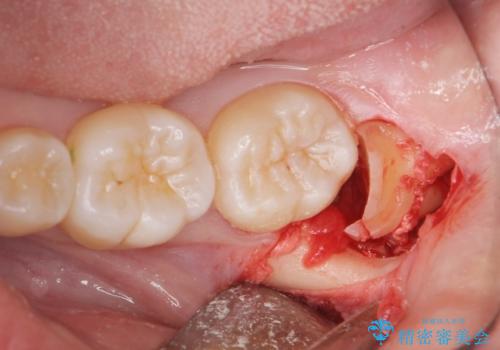

抜歯後、1週間後に抜糸を行う必要があります。

無事に親知らず抜歯ができました。

次回反対側の親知らずを抜歯するか検討中です。